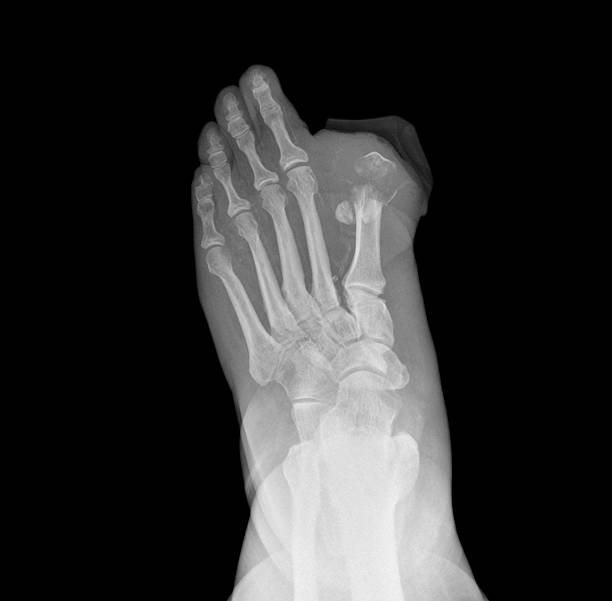

Суха гангрена – повільна, але небезпечна

Має повільний перебіг. Зазвичай розвивається через поступове зниження кровообігу, наприклад, при обмороженнях, діабеті, атеросклерозі. Суха гангрена з’являється на окремій ділянці тіла – вона поширюється повільно чи залишається стабільною тривалий час. Але й у такому випадку не виключений летальний кінець – особливо за наявності хронічних захворювань, які ослабляють організм.

Симптомами сухої гангрени вважаються:

- Зменшення розміру ураженої частини (висихання).

- Зміна кольору – від темно-синього до чорного.

- Відсутність болю на пізніх етапах.

- Чіткий кордон між здоровою та відмерлою тканиною.